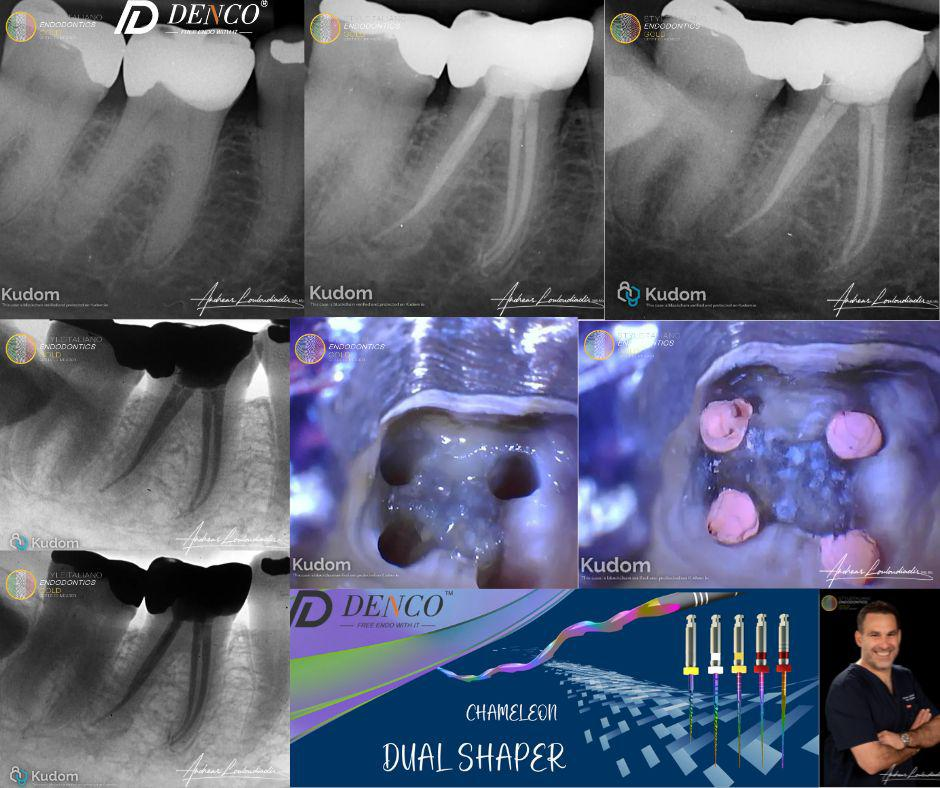

A case that was more challenging than what it looks like.

86-year-old female

Diagnosis: Pulp necrosis + symptomatic apical periodontitis

Clinical Challenge: Extremely calcified canals under a 50+ year-old crown with good margins and no decay. Extraction was not an option due to the patient’s injectable bisphosphonate therapy (risk of osteonecrosis) and overall frailty.

Access through existing crown and identified 4 highly sclerotic canals.

Conservative shaping using Denco Chameleon Dual Shaper file sequence.

Obturation: Bio-C BC sealer with hot modified technique.

Outcome: Clean, conservative RCT with minimal structural compromise — a true test of skill and precision.